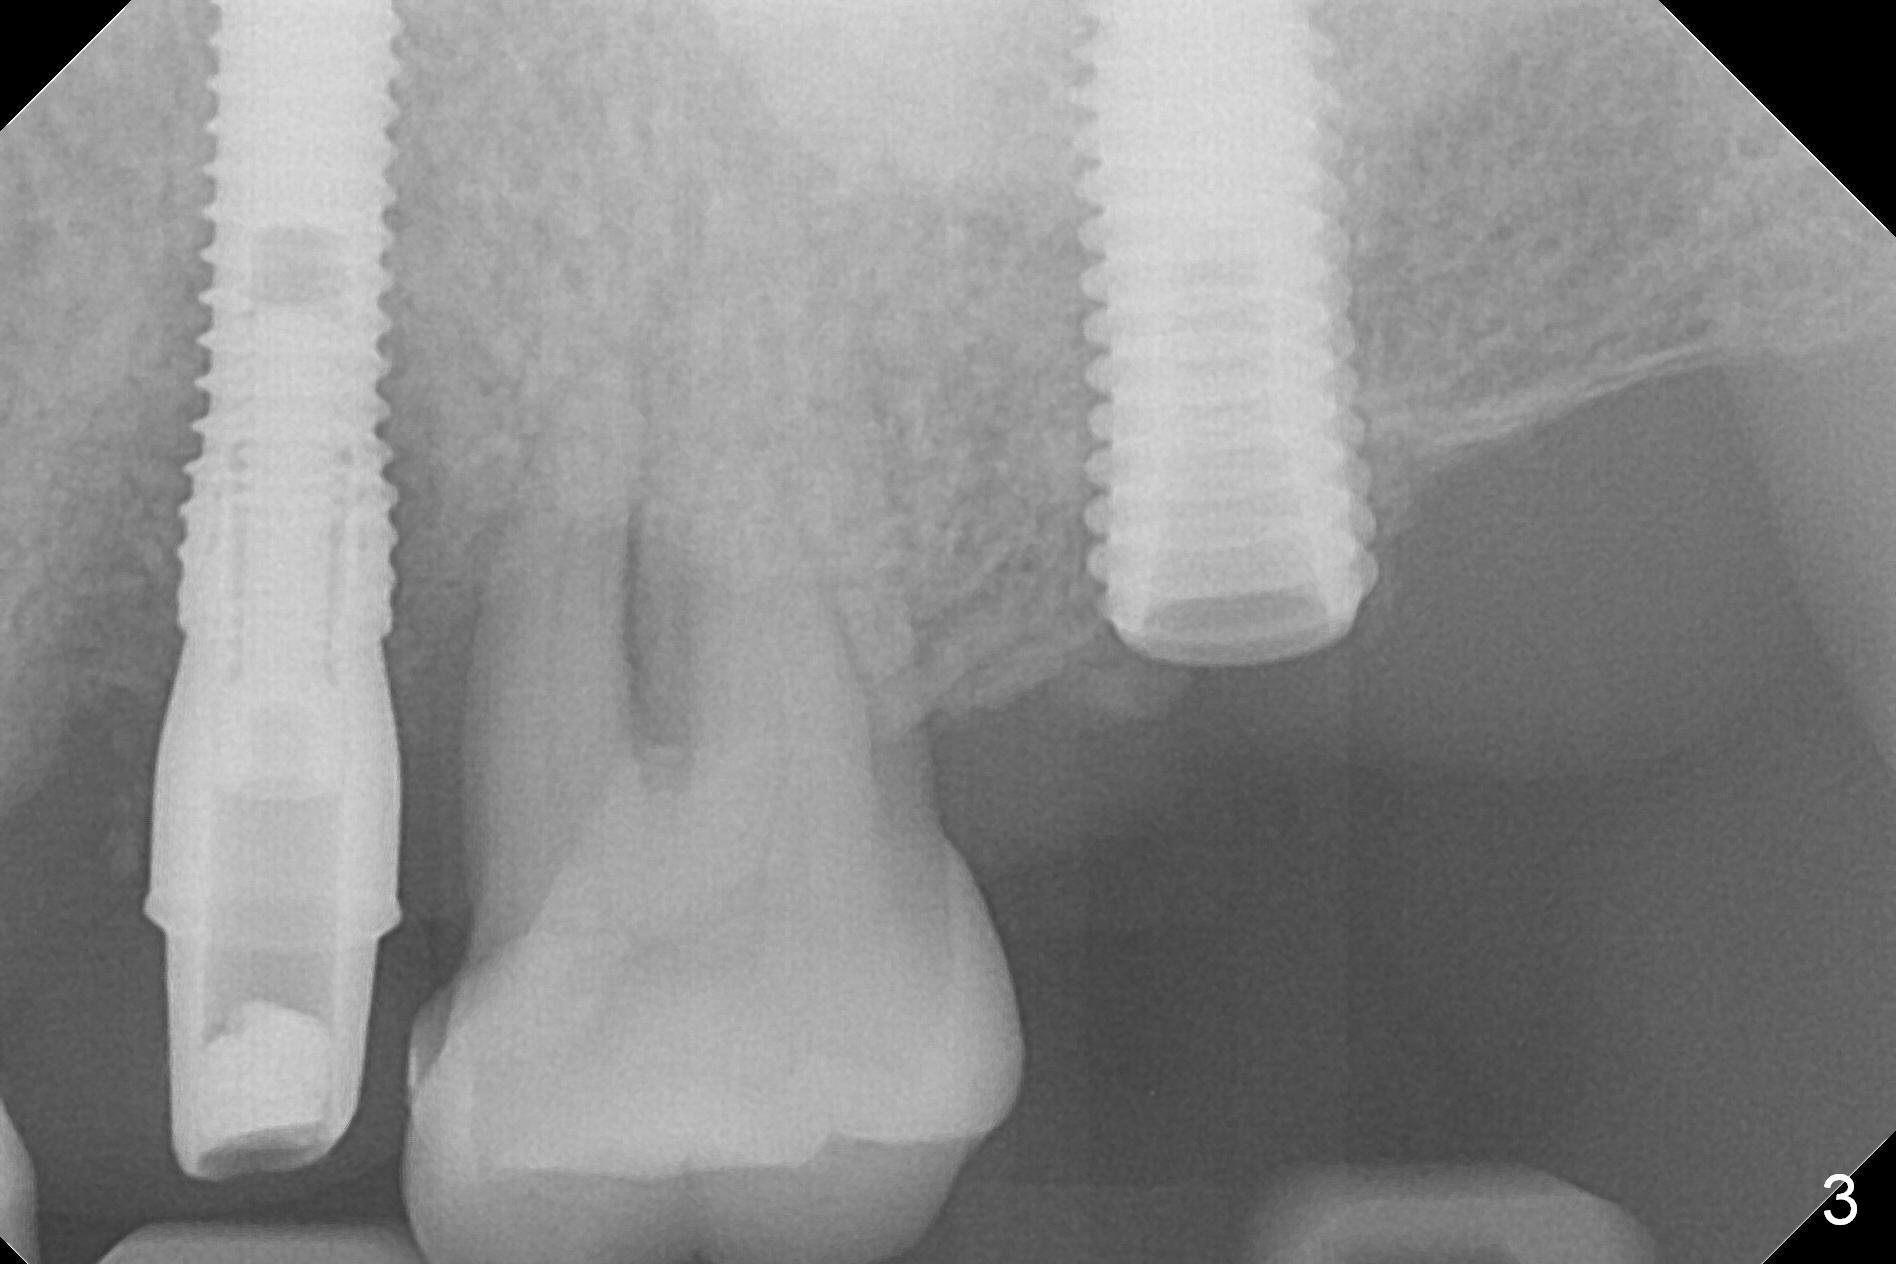

A 1.2 mm initial drill is used to start osteotomy at the site of #15 (Fig.1). After moving the osteotomy distally (with Lindamann bur), the osteotomy is enlarged by DIO Bone Expanders until 2.4/3.7 mm for 18 mm (gingival level) (Fig.2). Following the expander 3.0/4.4 mm, a 5x13 mm UF implant is placed supracrestal (Fig.3,4). After deepening the osteotomy with 3.8 mm drill for 3 mm, the implant is placed deeper by ~ 2 mm (Fig.5 arrow). Since the tooth #18 is supraerupted, a healing abutment (5.5x12(3) mm) is placed (Fig.6: H); the gingiva adapts to the abutment well. Suture is not necessary. The bone remains stable 2 and 4.5 months postop (Fig.7,8). Impression is taken. A crown is delivered nearly 6 months postop (08/07/2017). While there is minimal bone loss at #13 and 15 three years and 4 months post cementation, the tooth #14 and 18 are mobile (Fig.13,14, #13).